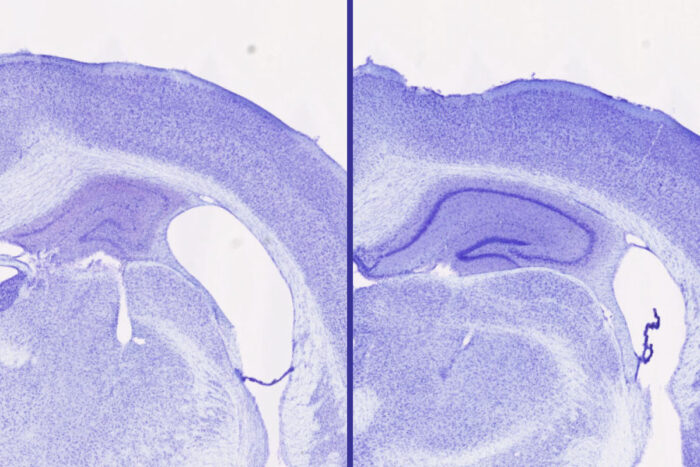

Samira Parhizkar/WashU Medicine

In mice genetically prone to harmful tau buildup, lemborexant reduced brain damage compared with control mice. For example, those receiving lemborexant showed 30% to 40% larger volume in the hippocampus — a part of the brain important for forming memories — compared with control mice and those receiving a different sleep drug, zolpidem, which belongs to a different class of drugs. Zolpidem increased sleep but had none of the protective effects against tau accumulation in the brain that were seen with lemborexant, suggesting that the type of sleep aid — orexin receptor antagonist — is key in producing the neuroprotective effects. The researchers also found that the beneficial effects were only seen in male mice, which they are still working to understand.